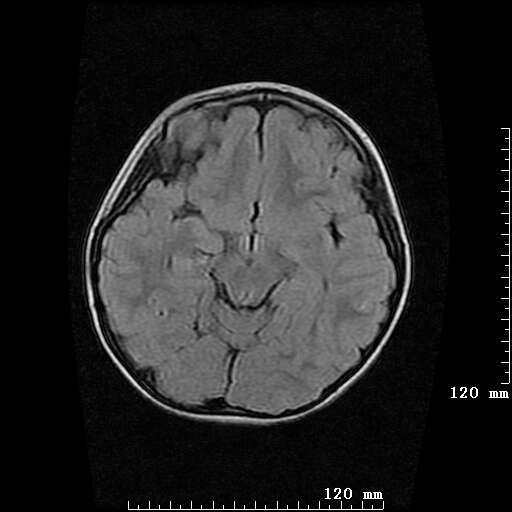

女,7岁,三岁才说话、走路。现智力尚可,走路不稳。临床怀疑大脑发育不全。

考虑 脑白质发育不良

脑折质变薄,双侧侧脑室稍扩张,支持考虑脑折质发育不良

侧脑室周围白质软化症。

考虑胼胝体发育不全,髓鞘形成不良。

支持考虑胼胝体发育不全,髓鞘形成不良。

脑裂畸形伴灰质异位

侧脑室周围白质数量减少,侧脑室不对称性扩大,左侧侧脑室后角呈方形改变,脑沟加深,结合临床考虑脑室周围白质软化症(pvl)。期待结果!

只看出灰质异位

支持脑白质发育不良。